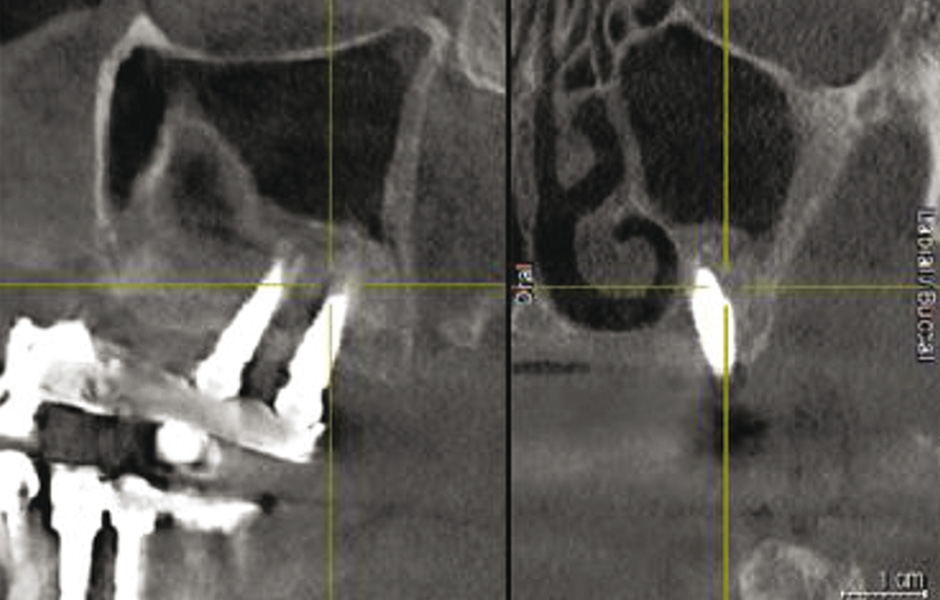

Obr. 1: CBCT: radiopakní stín v levém maxilárním sinu.

Do studie bylo zařazeno 10 pacientů s aspergilózou maxilárního sinu. U všech pacientů byl na panoramatických snímcích i na CBCT patrný radiopakní stín. CBCT navíc ukázalo, že čelistní dutina byla kompletně vyplněna homogenní patologickou masou. Chirurgická léčba sinu byla provedena za antibiotické profylaxe (Amoxicillin 2 g/den po dobu 7 dní) a intravenózní sedace (Midazolam). Kostní okénko bylo vytvořeno mikropilkou (DENTSPLY Implants), umožnilo bezpečný přístup do sinu. Po odklopení separovaného kostního fragmentu byla aspergilóza spolu s cizorodým materiálem kompletně odstraněna a dutina vypláchnuta peroxidem vodíku (H₂O₂ 3 %). Pro dodatečnou dezinfekci byla použita fotodynamická dekontaminace laserem HELBO (HELBO, Bredent Medical GmbH). Na závěr zákroku byla kostěná lamela vrácena zpět jako biologický uzávěr sinu a fixována resorbovatelnými stehy. Histopatologické vyšetření ve všech případech potvrdilo infekci aspergilózou. Po třech měsících, kdy CBCT potvrdilo nepřítomnost sinusové patologie a průchodné ostium, byla provedena augmentace kosti. Kostní bloky byly odebrány z retromolárové oblasti mandibuly a přeneseny ve 3D konfiguraci podle split-bone block techniky v kombinaci se sinus liftem. Sinus byl augmentován autologní kostí a biomateriálem (FRIOS Algipore®, DENTSPLY Implants) vrstvenou technikou. Po dalších třech měsících byly do augmentované oblasti zavedeny implantáty. O další tři měsíce později byly implantáty odhaleny a následně byla zhotovena definitivní protetická náhrada.“